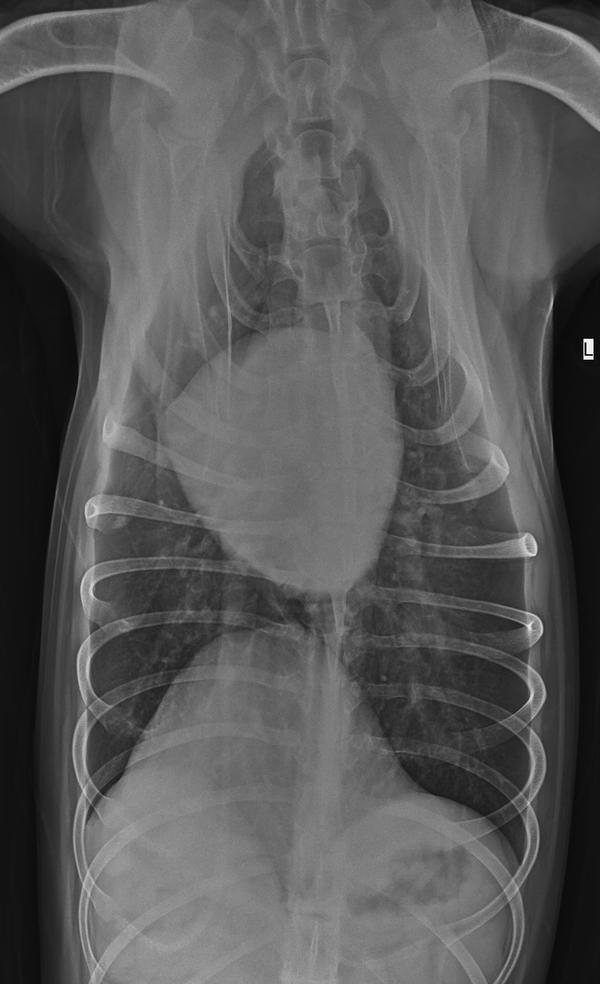

到医院后医院没有仔细看资料,开了7个检查“生化、血常规、4张X光、1组B超、胰腺炎测试、C反、粪便化验”,就是不肯做胃镜检查。宠物主人不好意思反对医生的意见所以7个化验花了2000元。化验结果和我们预料的一样,每一个都没有问题,甚至可以说狗的身体结果是完美的,血常规和生化里没有任何一项指标高或者低(健康狗里都很少),其中2张片子还是照心脏的。